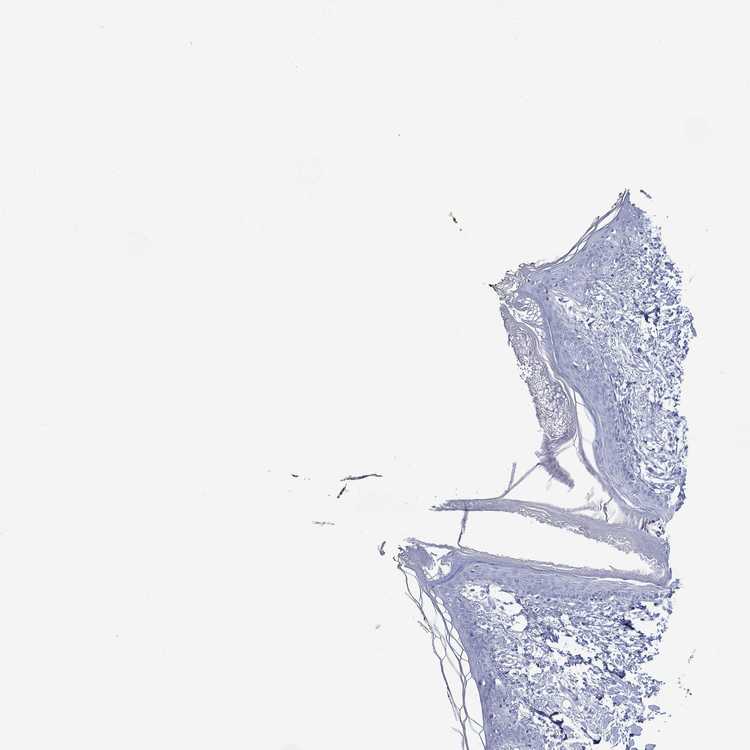

TISSUE PRIMARY DATA SKIN Show tissue menu

SKIN 1 - Antibody stainingi

Antibody staining in the annotated cell types in the current human tissue is reported as not detected, low, medium, or high, based on conventional immunohistochemistry profiling in selected tissues. This score is based on the combination of the staining intensity and fraction of stained cells.

Each image is clickable and will lead to virtual microscopy that enables deeper exploration of all samples and also displays staining intensity scores, fraction scores and subcellular localization as well as patient and tissue information for each sample.

Antibody HPA079482

Langerhans Not detected

Fibroblasts Not detected

Keratinocytes Not detected

Melanocytes Not detected

SKIN 2 - Antibody stainingi

Epidermal cells Not detected